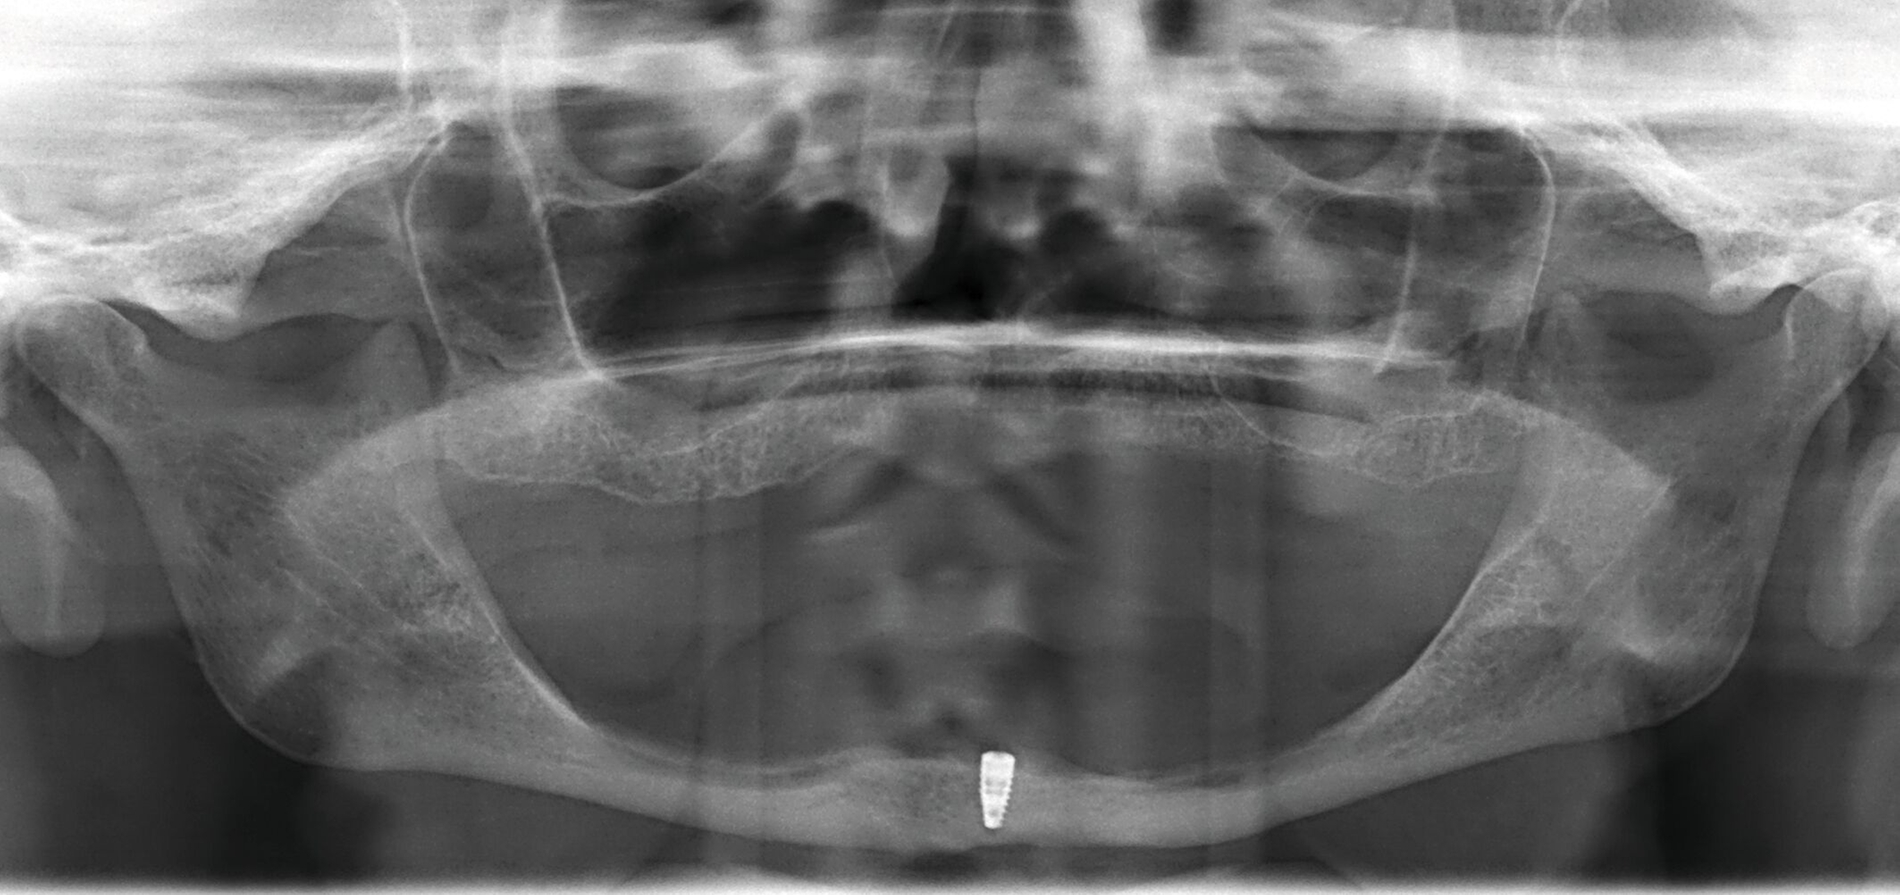

Ein überschaubares, pflegeleichtes und zudem preiswertes Konzept ist das mittig stehende einzelne Implantat zur Stabilisierung der totalen Unterkiefer-Prothese. Die erste Fünf-Jahres-Studie hierzu aus dem Jahr 1997 berichtet über eine Implantatüberlebensrate von 100 Prozent bei 21 Patienten mit einem mittleren Alter von 74,2 Jahren [Cordioli et al., 1997]. Die hohe Implantatüberlebensrate wurde inzwischen von zahlreichen Studien bestätigt [Padmanabhan et al., 2020]. Die Matrizen auf Kugelankern oder anderen Druckknopf-artigen Elementen werden in der Regel kostensparend direkt in die vorhandene Prothese einpolymerisiert (Abbildung 2).